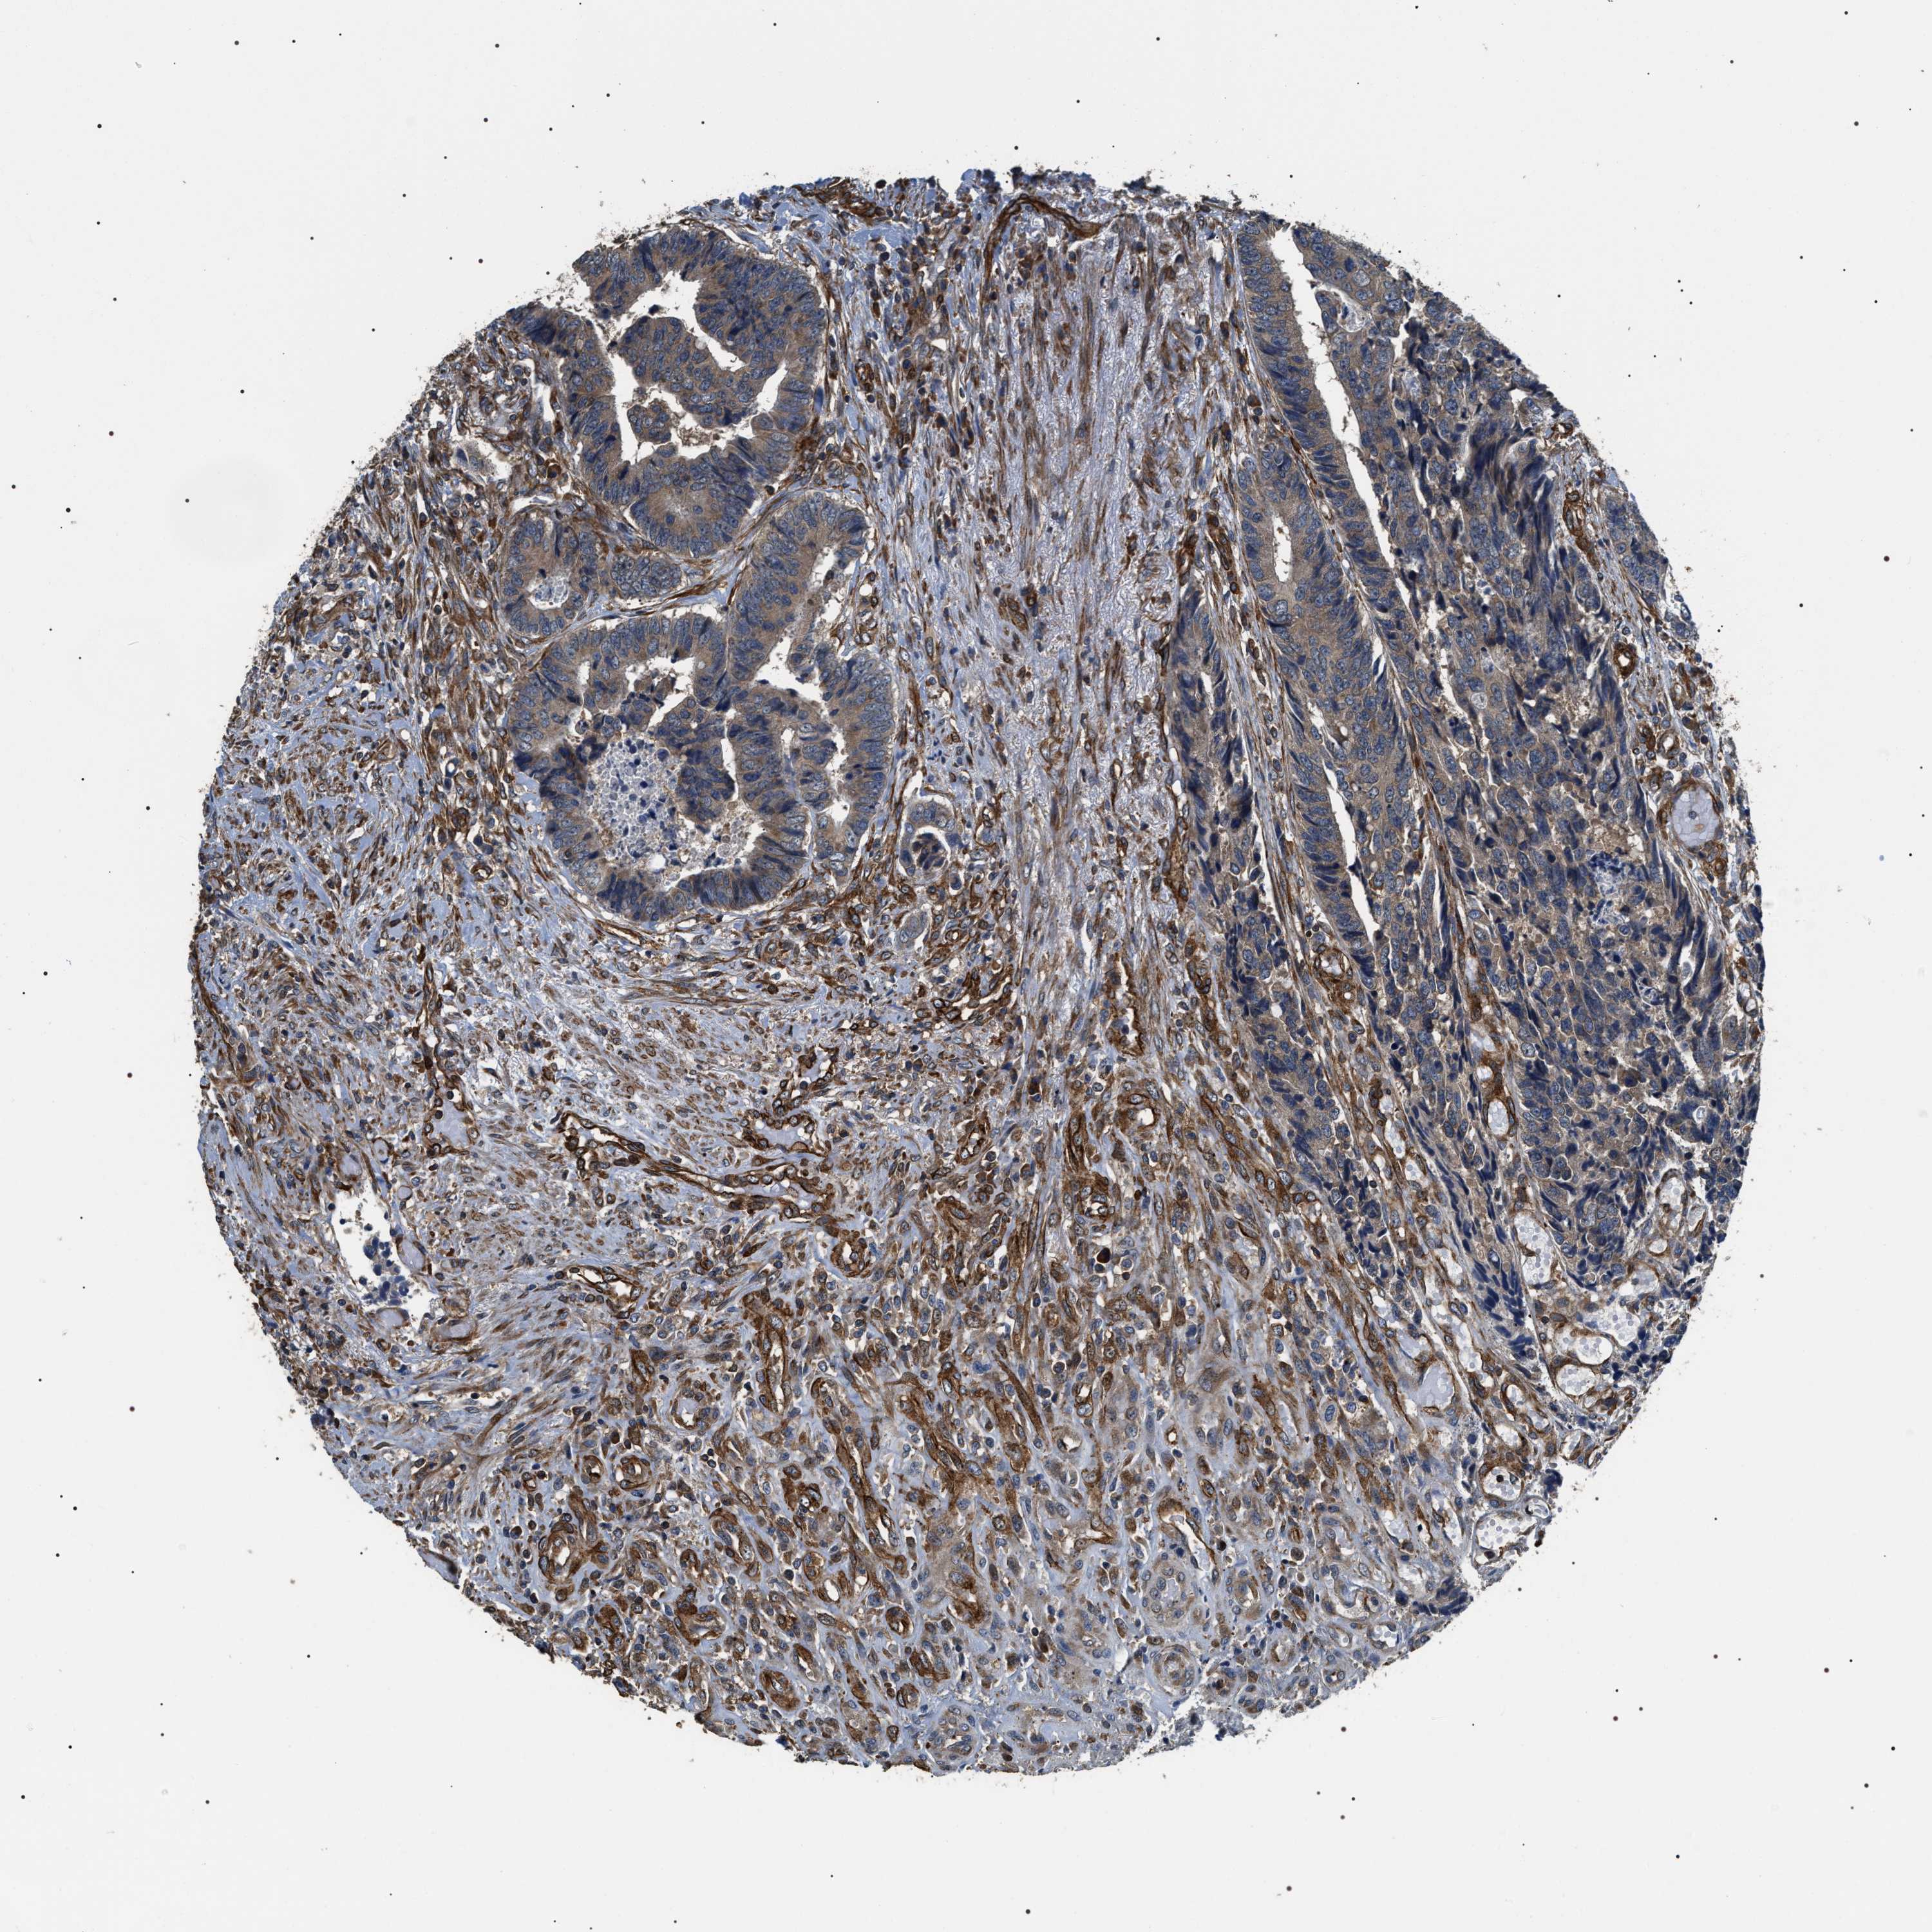

COLON ADENOCARCINOMA (TCGA) - Interactive survival scatter ploti

The Survival Scatter plot shows the clinical status (i.e. dead or alive) for all individuals in the patient cohort, based on the same data that underlies the corresponding Kaplan-Meier plots. Patients that are alive at last time for follow-up are shown in blue and patients who have died during the study are shown in red.

The x-axis shows the expression levels (FPKM) of the investigated gene in the tumor tissue at the time of diagnosis. The y-axis shows the follow-up time after diagnosis (years). Both axes are complimented with kernel density curves demonstrating the data density over the axes. The top density plot shows the expression levels (FPKM) distribution among dead (red) and alive patients (blue). The right density plot shows the data density of the survived years of dead patients with high and low expression levels respectively, stratified using the cutoff indicated by the vertical dashed line through the Survival Scatter plot. This cutoff is automatically defined based on the FPKM cutoff that minimizes the p-score. The cutoff can be changed by dragging the vertical line or by entering a cutoff value in the square labeled "Current cut-off".

Under the Survival Scatter plot the p-score landscape (black curve; left axis) is shown together with dead median separation (red curve; right axis). Dead median separation is the difference in median mRNA expression between patients who have died with high and low expression, respectively. It is calculated as follows: median FPKM expression of dead patients with high expression - median FPKM expression of dead patients with low expression. This is intended to aid the user in visually exploring custom cutoffs and the associated p-scores and dead median separation.

Individual patient data is displayed and can be filtered by clicking on one or more of the category buttons on the top of the page. Categories describing expression level and patient information include: high, low, alive, dead, female, male and tumor stages. The scale of the x-axis can be toggled between linear and log-scale by clicking on the "x log" button. Mouse-over function shows TCGA ID, patient information and mRNA expression (FPKM) for each patient.

& Survival analysisi

Kaplan-Meier plots summarize results from analysis of correlation between mRNA expression level and patient survival. Patients were divided based on level of expression into one of the two groups "low" (under cut off) or "high" (over cut off). X-axis shows time for survival (years) and y-axis shows the probability of survival, where 1.0 corresponds to 100 percent.

ZC3HAV1L is not prognostic in Colon Adenocarcinoma (TCGA)

Best expression cut offi

Based on the FPKM value of each gene, patients were classified into two groups and association between prognosis (survival) and gene expression (FPKM) was examined. The best expression cut-off refers the FPKM value that yields maximal difference with regard to survival between the two groups at the lowest log-rank P-value. Best expression cut-off was selected based on survival analysis .

When clicking on this number, the vertical dashed line indicating cut-off, the interactive survival plot, and the Kaplan-Meier curve will be adjusted to show results based on the best expression cut-off.

: 6.01

Median expressioni

Median expression refers to the median FPKM value calculated based on the gene expression (FPKM) data from all patients in this dataset. When clicking on this number, the vertical dashed line indicating cut-off, the interactive survival plot, and the Kaplan-Meier curve will be adjusted to show results based on the median expression.

: N/A

P scorei

Log-rank P value for Kaplan-Meier plot showing results from analysis of correlation between mRNA expression level and patient survival.

N/A

5-year survival highi

5-year survival for patients with higher expression than the expression cutoff.

For melanoma and glioma, 3-year survival is shown.

5-year survival lowi

5-year survival for patients with lower expression than the expression cutoff.

TCGA RNA samplesi

RNA-seq data is reported as average FPKM (number Fragments Per Kilobase of exon per Million reads), generated by the The Cancer Genome Atlas (TCGA) .

Normal distribution across the dataset is visualized with box plots, shown as median and 25th and 75th percentiles. Points are displayed as outliers if they are above or below 1.5 times the interquartile range. FPKM values of the individual samples are presented next to the box plot.

Average pTPM 5.3

Number of samples 254